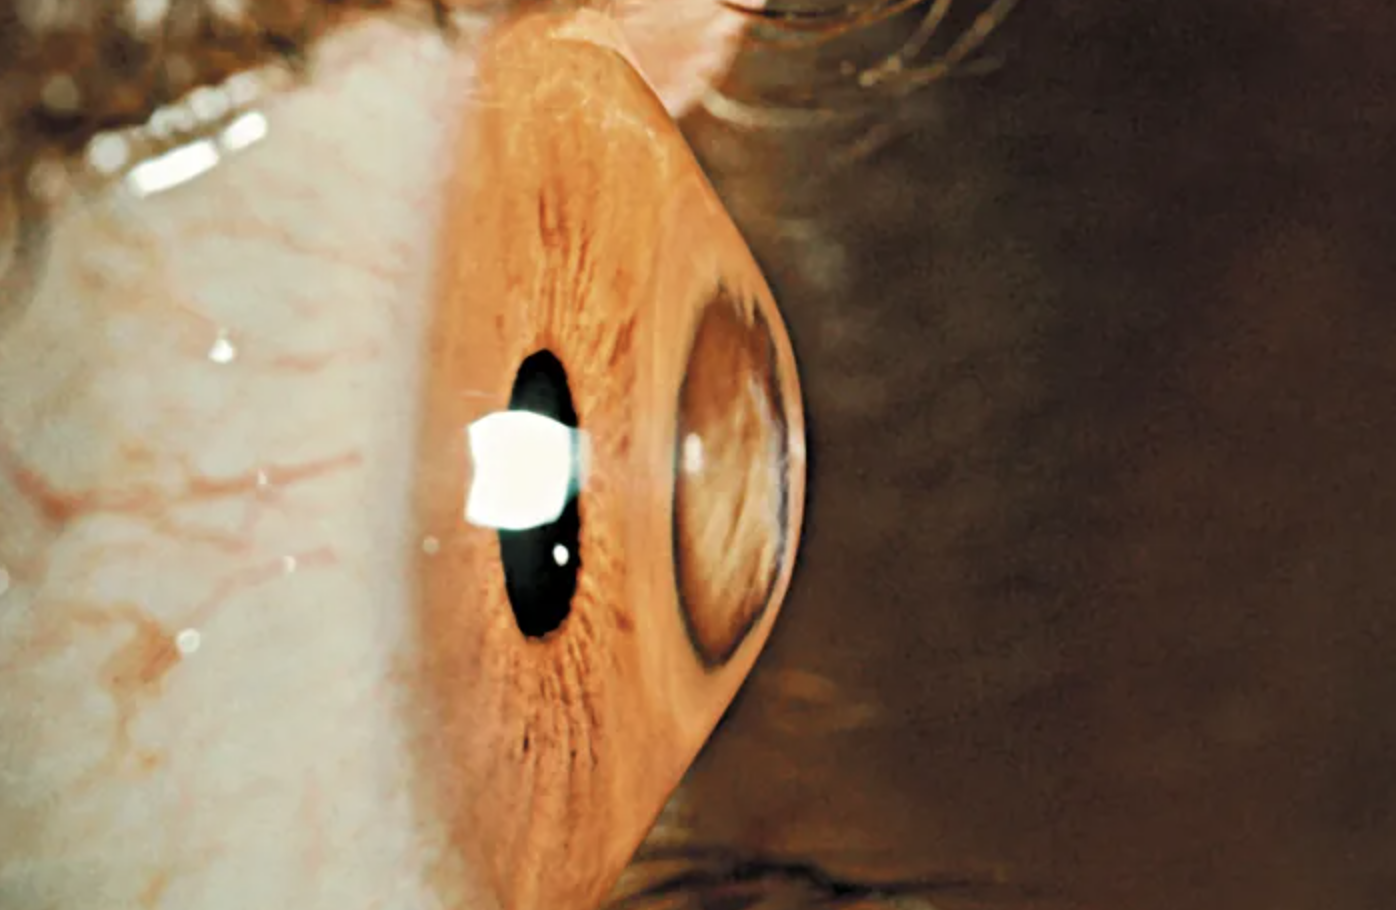

Η εν λόγω νόσος είναι ο κερατόκωνος, κατά τον οποίο παρατηρείται παθολογική λέπτυνση του κολλαγόνου στον κερατοειδή χιτώνα του οφθαλμού. Η λέπτυνση προκαλεί αστάθεια και αλλαγή του σχήματος του κερατοειδούς, ο οποίος από σχεδόν σφαιρικός γίνεται κωνικός.

Ο κωνικός κερατοειδής έχει πολύ λεπτό πάχος, καθώς μειώνεται κεντρικά από τα φυσιολογικά 550 μικρόμετρα (μm) μέχρι και 300 μm. Το μικρόμετρο (ή μικρόν) ισούται με ένα εκατομμυριοστό του μέτρου. Ο κωνικός κερατοειδής έχει επίσης σημαντικά παραμορφωμένη πρόσθια και οπίσθια επιφάνεια.

Οι αλλαγές αυτές προκαλούν μη ομαλή και σημαντικά αυξημένη κυρτότητα, συνήθως παράκεντρα. Αυτό δημιουργεί συνήθως μυωπία και σημαντικό αστιγματισμό. Ένας τέτοιος κερατοειδής έχει ως αποτέλεσμα η διάθλαση του φωτός στον οφθαλμό να είναι ανώμαλη και το είδωλο να είναι πολύ ασαφές (διπλό, πηγές φωτός με «ουρές»).